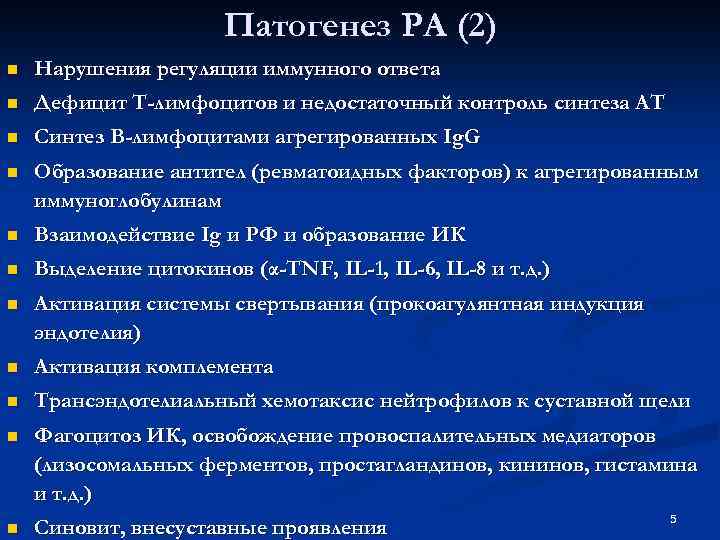

Патогенез РА (2) n Нарушения регуляции иммунного ответа n Дефицит Т-лимфоцитов и недостаточный контроль синтеза АТ n Синтез В-лимфоцитами агрегированных Ig. G n Образование антител (ревматоидных факторов) к агрегированным иммуноглобулинам n Взаимодействие Ig и РФ и образование ИК n Выделение цитокинов (α-TNF, IL-1, IL-6, IL-8 и т. д. ) n Активация системы свертывания (прокоагулянтная индукция эндотелия) n Активация комплемента n Трансэндотелиальный хемотаксис нейтрофилов к суставной щели n Фагоцитоз ИК, освобождение провоспалительных медиаторов (лизосомальных ферментов, простагландинов, кининов, гистамина и т. д. ) n Синовит, внесуставные проявления 5

Патогенез РА (2) n Нарушения регуляции иммунного ответа n Дефицит Т-лимфоцитов и недостаточный контроль синтеза АТ n Синтез В-лимфоцитами агрегированных Ig. G n Образование антител (ревматоидных факторов) к агрегированным иммуноглобулинам n Взаимодействие Ig и РФ и образование ИК n Выделение цитокинов (α-TNF, IL-1, IL-6, IL-8 и т. д. ) n Активация системы свертывания (прокоагулянтная индукция эндотелия) n Активация комплемента n Трансэндотелиальный хемотаксис нейтрофилов к суставной щели n Фагоцитоз ИК, освобождение провоспалительных медиаторов (лизосомальных ферментов, простагландинов, кининов, гистамина и т. д. ) n Синовит, внесуставные проявления 5